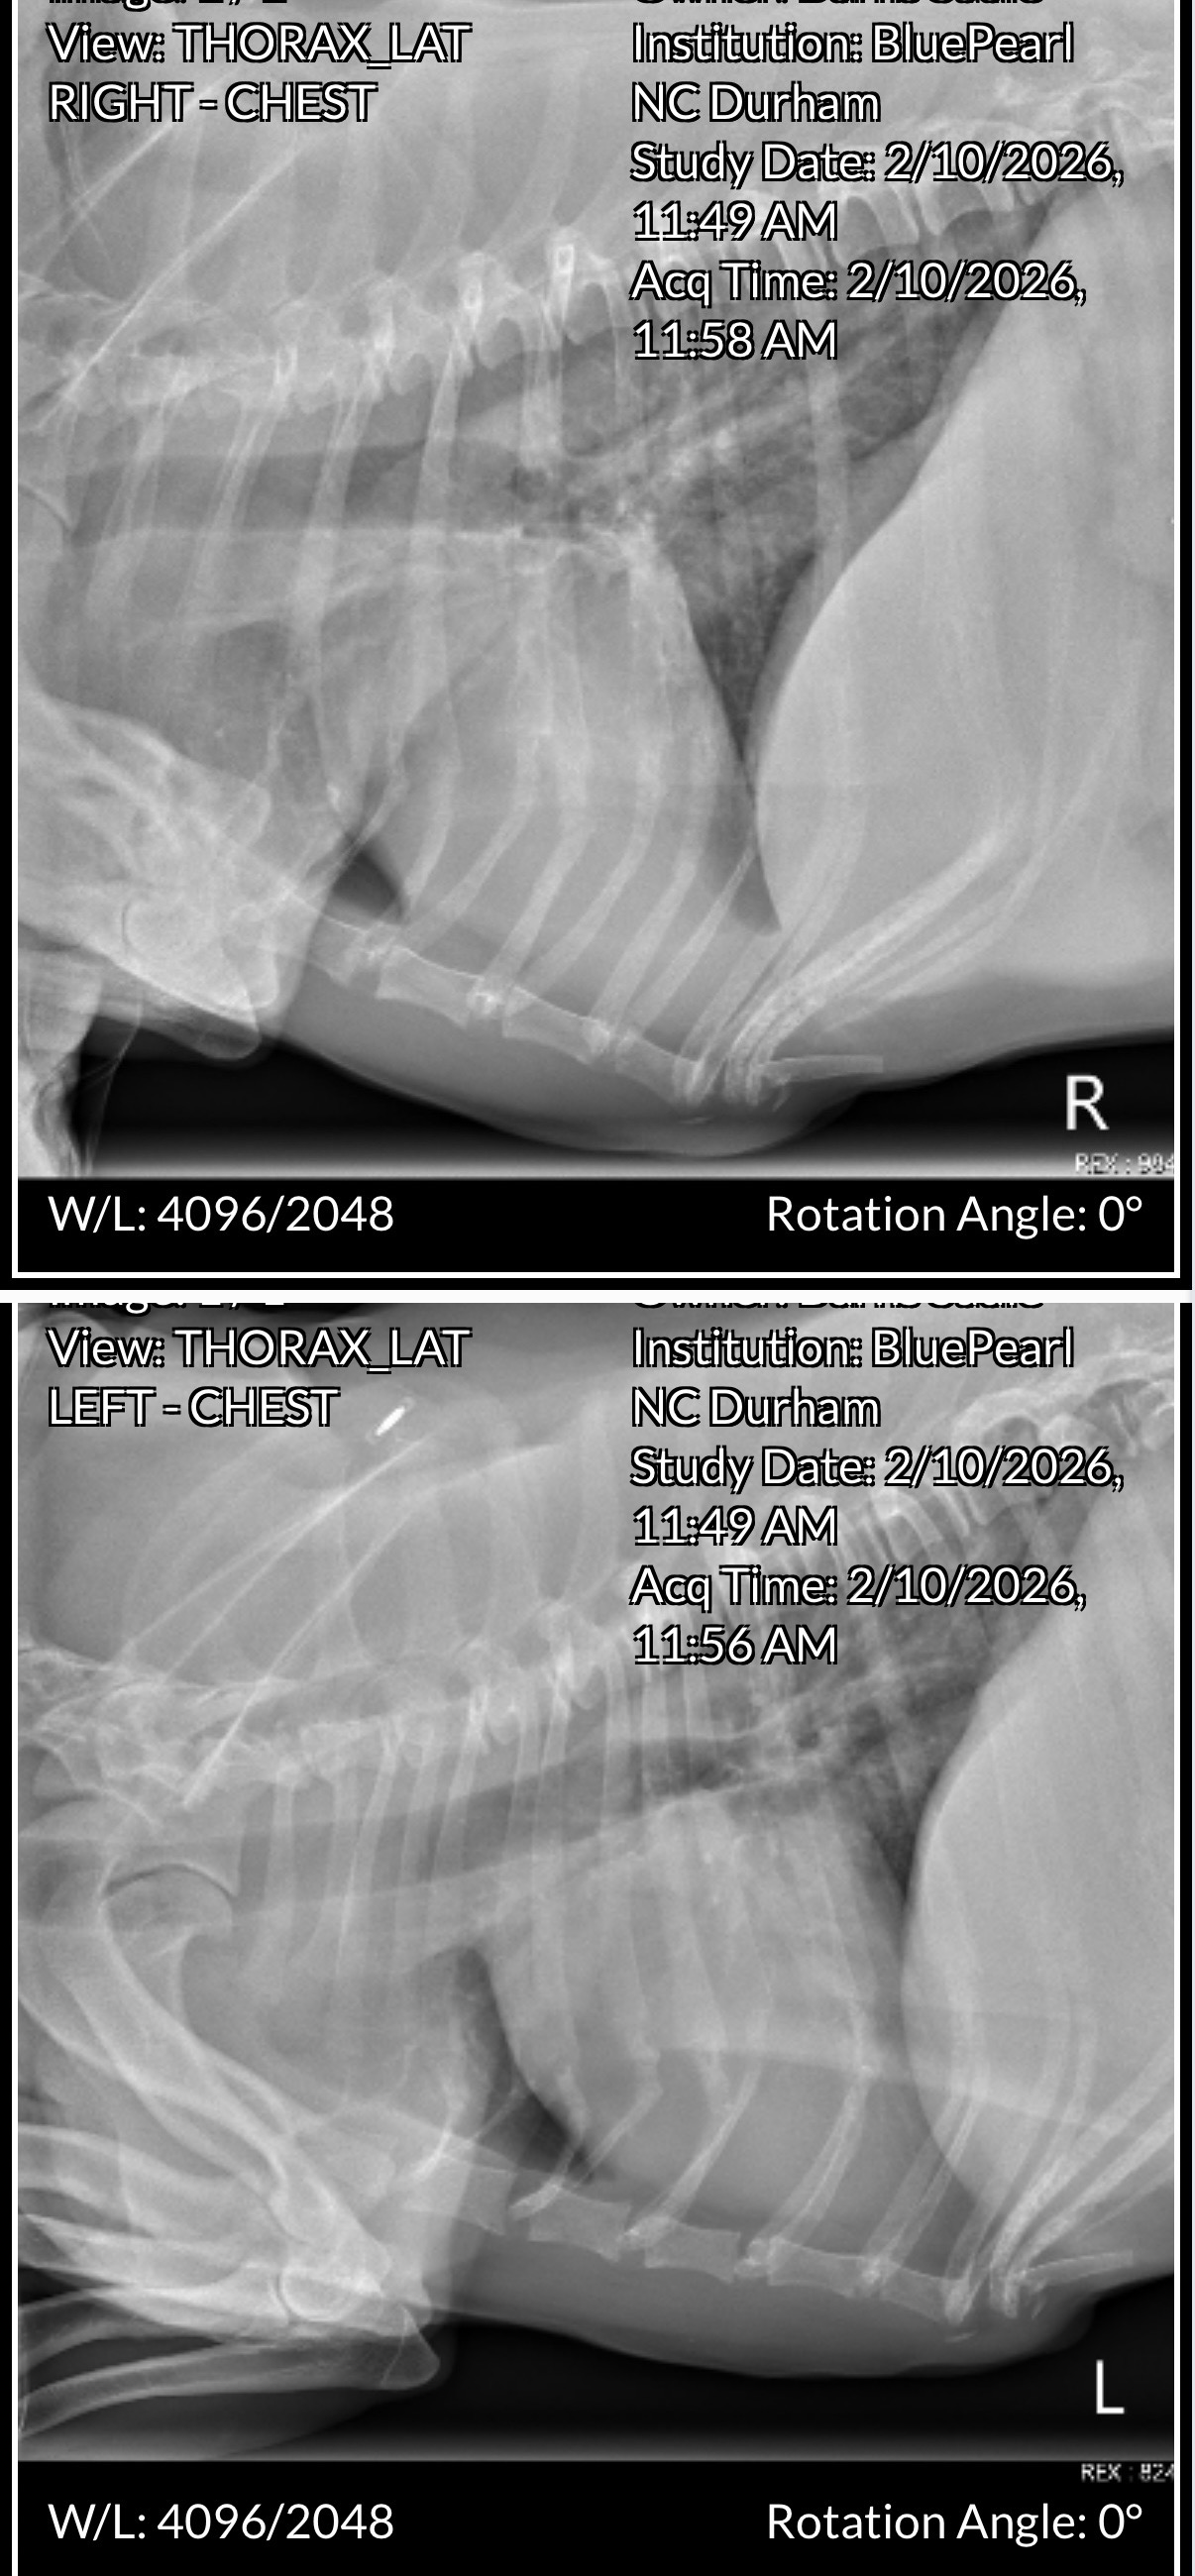

On Monday, 2/9/26, Sadie suddenly collapsed at home. It looked like a seizure, and I rushed her to the emergency vet. After a long night and a series of tests and administered medications, followed by more tests the following day-bloodwork, panels, X-rays, and 2 different types of ultrasounds—the vets discovered she has a heart arrhythmia and a large tumor on her spleen. Her liver is also slightly enlarged and showing elevated enzymes. On Friday 2/13, she got an echocardiogram to further explore why she collapsed, look into why she has an arrhythmia, and see if she would be able to handle surgery. She was cleared for her splenectomy and after surgery, her spleen/tumor and liver will be biopsied to find out more and go from there and possibly need treatment.